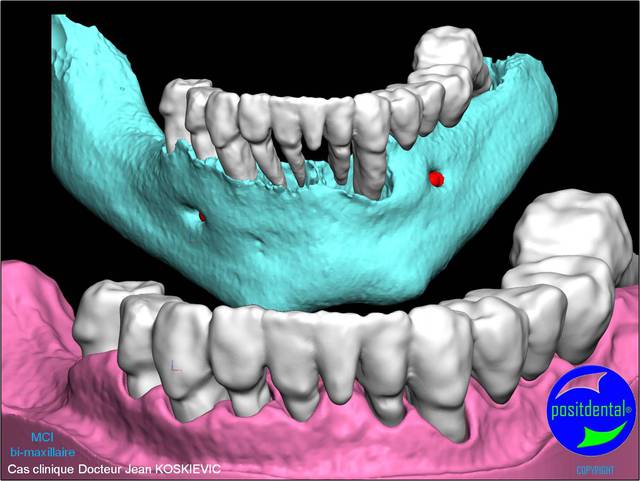

rendu 3D maxillaire sup, pano et photo

3D maxillaire inférieur et photo

Montage esthétique ou wax-up 3D